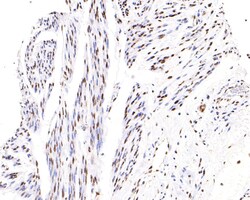

Invitrogen™ Phospho-ATF2 (Thr71) Recombinant Rabbit Monoclonal Antibody (SC05-90)

The transcription factor ATF-2 (also called CRE-BP1) binds to both AP-1 and CRE DNA response elements and is a member of the ATF/CREB family of leucine zipper proteins. ATF-2 interacts with a variety of viral oncoproteins and cellular tumor suppressors and is a target of the SAPK/JNK and p38 MAP kinase signaling pathways. Various forms of cellular stress, including genotoxic agents, inflammatory cytokines and UV irradiation, stimulate the transcriptional activity of ATF-2. Cellular stress activates ATF-2 by phosphorylation of Thr69 and Thr71. Both SAPK and p38 MAPK have been shown to phosphorylate ATF-2 at these sites in vitro and in cells transfected with ATF-2.

| Immunohistochemistry (Paraffin), Western Blot, Immunocytochemistry | |